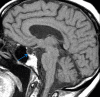

Figure 1. MRI showing empty sella.